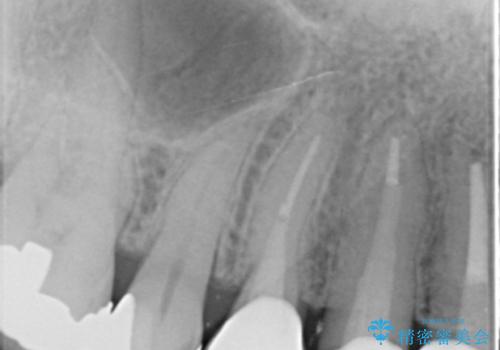

- 若い時に作った前歯のブリッジがの根元が黒くなってきているとのことで来院。

支える歯が1本虫歯がひどく、割れていました。

根の治療からやり直して新しいブリッジにしています。

ブリッジの支台歯は、根の再治療を含めて行なっています。